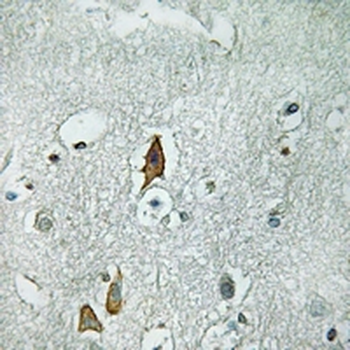

Immunohistochemical analysis of CD125 staining in human brain formalin fixed paraffin embedded tissue section. The section was pre-treated using heat mediated antigen retrieval with sodium citrate buffer (pH6.0). The section was then incubated with the antibody at room temperature and detected using an HRP conjugated compact polymer system. DAB was used as the chromogen. The section was then counterstained with haematoxylin and mounted with DPX.